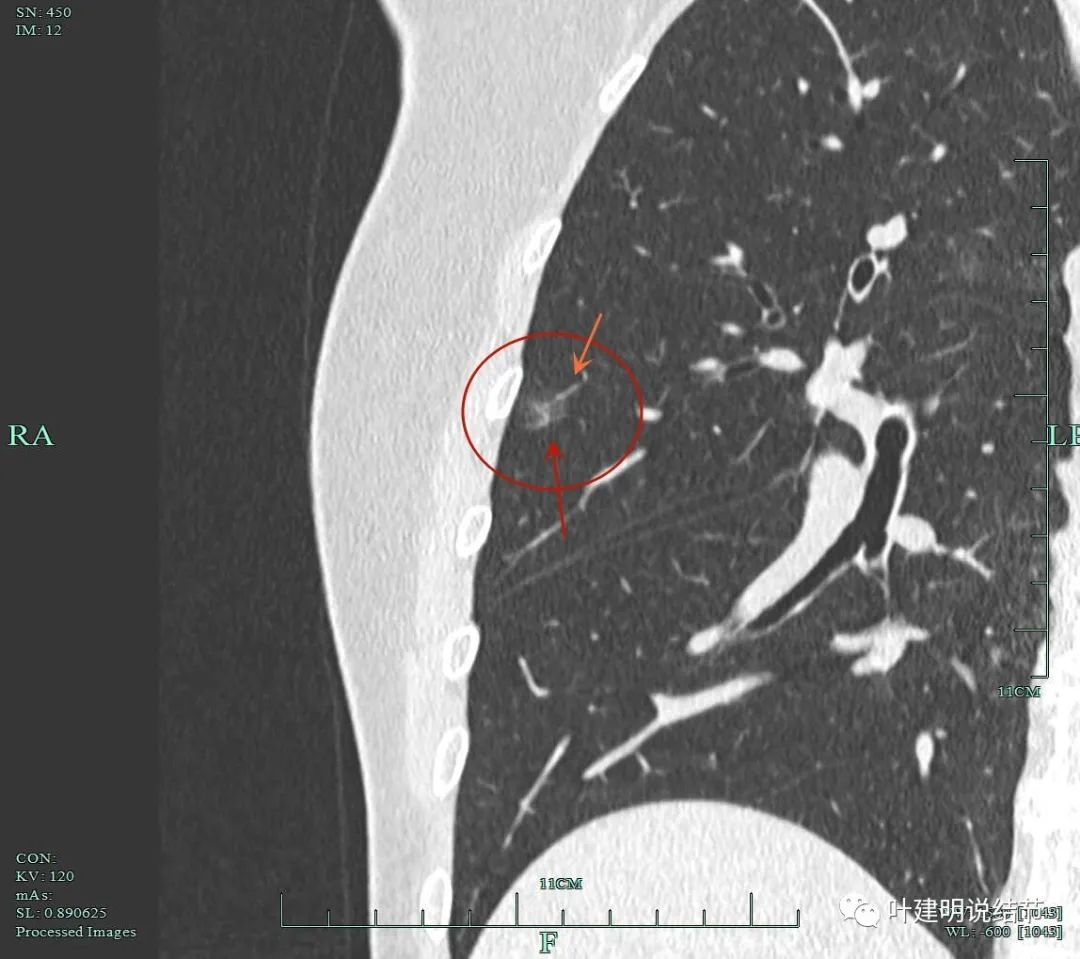

靶重建影像展示:

病灶6重建后显示血管进入与穿行。

病灶2重建后显示瘤肺边界清以及血管进入。

病灶8重建后显示血管与结节间没有间隙,而且瘤肺边界很清。